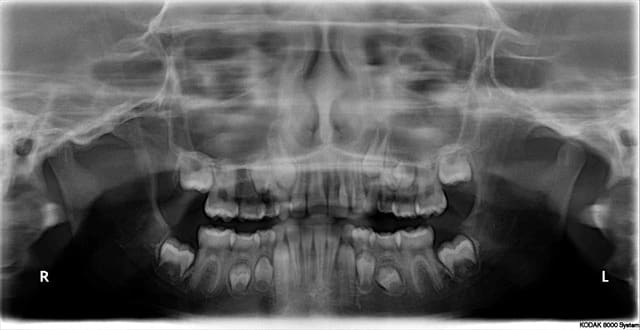

je fais appel à vous (ODF) pour le cas de ce jeune patient de 9 ans qui présente plusieurs agénésies.

Ici c'est sa soeur âgée de 11 ans agénésie de 15 et 22 surnuméraire (déjà extraite car évoluant au palais)

Je ne fais pas d'odf, mais si je devais établir un plan de ttt pour ce patient à la seule vue de la pano, ce serai extraction des 4 "5" lactéales et fermeture des espaces, et envisager un implant en place de 44, le plus tard possible si la 84 tient le coup. Ce serai amha le meilleur compromis.

diastème 11/21 les 22 et 12 pas sorties sans doute vestibulées, j'ai du extraire la 62 précocément du fait de sa version prononcée: espace 53/11 2,5 mm idem pour 21/63.